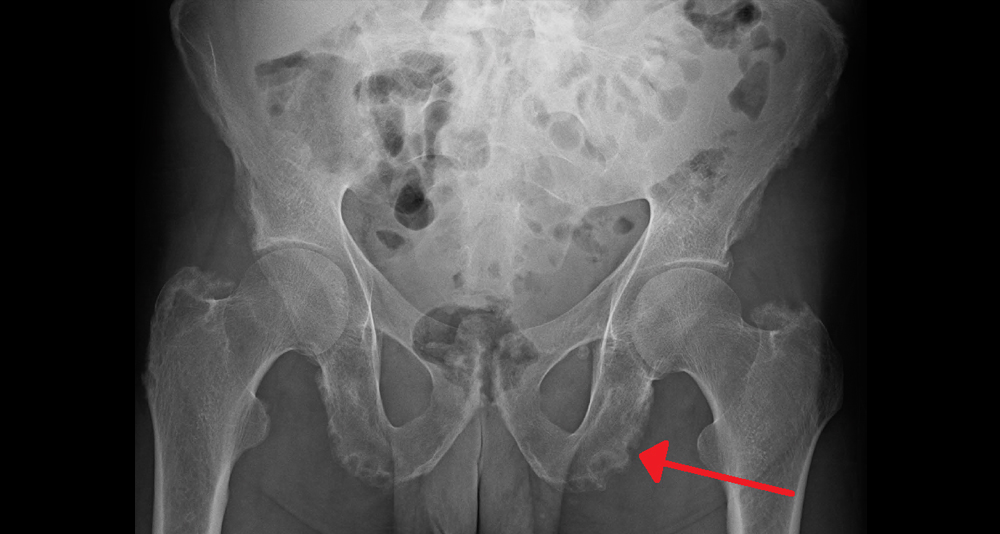

Causes of a Broken Pelvis typically involve high-impact trauma or weakened bone structure. The most common causes of a broken pelvis include road accidents, falls from height, sports injuries, osteoporosis, and crushing incidents. Identifying the cause is crucial for both emergency treatment and future prevention.

Motor vehicle collisions are the leading cause of pelvic fractures. In severe crashes, the force transmitted through the dashboard, seatbelt, or impact with external objects can compress the pelvis and cause multiple breaks. Cyclists and motorcyclists are particularly vulnerable due to limited protection.

Falls from height — such as ladders, scaffolding, or stairs — are another major contributor. When a person lands on their feet or buttocks from a height, the energy travels through the legs and into the pelvis, potentially causing compression fractures.

Older adults with osteoporosis are at high risk of pelvic fractures from even minor falls. This is because reduced bone density makes the pelvis more fragile and susceptible to breaks from low-energy impacts, such as tripping over a rug or slipping on wet tiles.